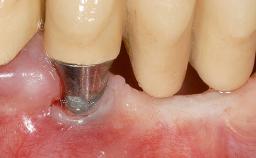

Implant Placement in the Esthetic Zone and Coverage of Multiple Gingival Recessions

This case illustrates use of a modified ‘tunnel’ technique, which has been shown to be highly effective in root coverage procedures. The tunnel technique is used to achieve soft-tissue augmentation across the anterior area, including the planned implant site, using collagen matrix as grafting material. The patient is a 47-year-old woman with high esthetic expectations. Her main concern was the appearance of the anterior teeth and their “elongation”.

Soft Tissue Grafting Staged

Loading Protocol Immediate